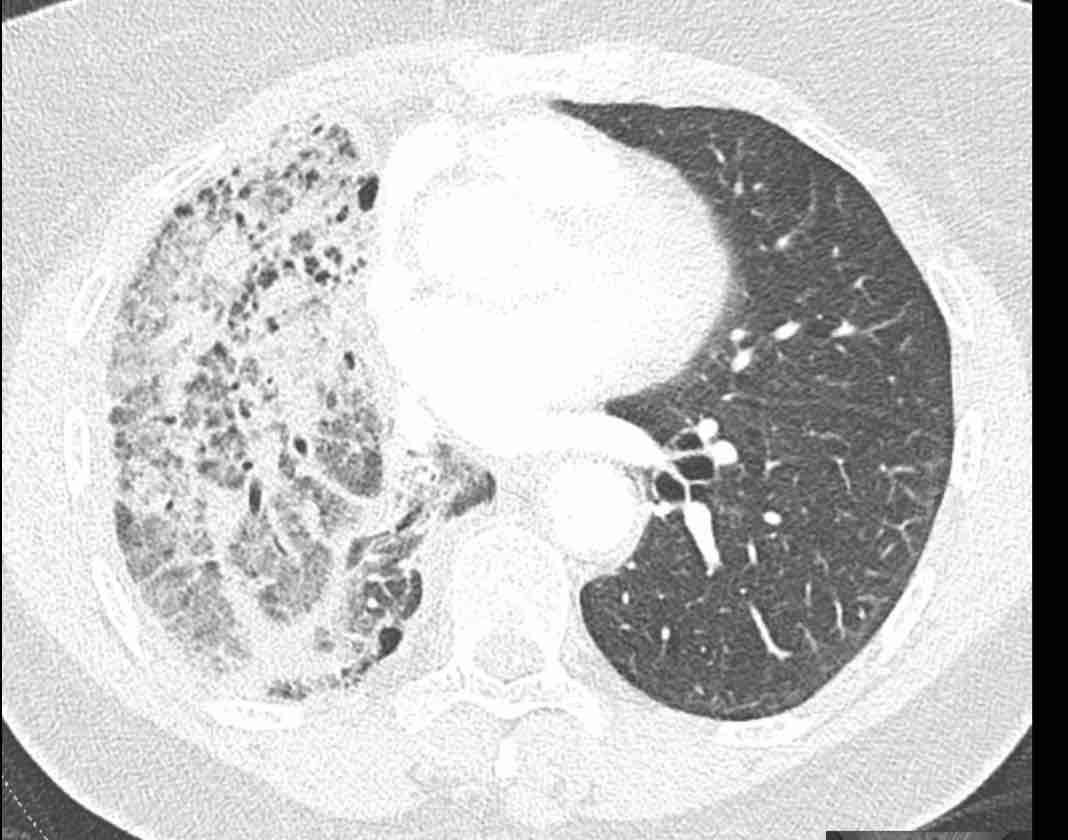

Hình ảnh

Cuộn qua các hình ảnh.

Theo dõi các phế quản của thùy dưới phổi trái cho thấy nhánh phân thùy đầu tiên của thùy dưới phổi trái còn thông; đó là phế quản phân thùy đỉnh.

Các ghim phẫu thuật nằm tại vị trí của các phân thùy đáy sau và đáy bên (LB9/10), vốn thường được cắt bỏ cùng nhau.

Do đó, phân thùy phổi có hình ảnh kính mờ và đông đặc phải là phân thùy đáy trước của thùy dưới phổi trái (LB8).

Động mạch phổi đến phân thùy này cũng không ngấm thuốc cản quang, và bản đồ tưới máu iốt nhấn mạnh thêm tình trạng nhồi máu.

Bệnh nhân đã được phẫu thuật lại và tiến hành cắt bỏ phân thùy bị nhồi máu, với xác nhận qua giải phẫu bệnh.

Tiếp tục với bản đồ tưới máu…

Trên bản đồ tưới máu iốt, có sự tưới máu ở thùy trên phổi trái và phân thùy đỉnh của thùy dưới phổi trái, nhưng không có sự tưới máu ở phân thùy đáy trước của thùy dưới phổi trái.